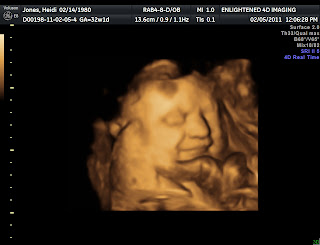

3D Ultrasound

Nate here...

I remember when Meredith got this done awhile back and how freaky I thought it was. I still think it is pretty freaky but can't thank you enough Meredith for the gift of this. It was great to see the little guy in there one more time before he decided to get out of there. Heidi and I felt so rushed at our last ultrasound and were disappointed in that that may have been the last time we could get a look at him. Anyway, thanks! Enjoy the pics!